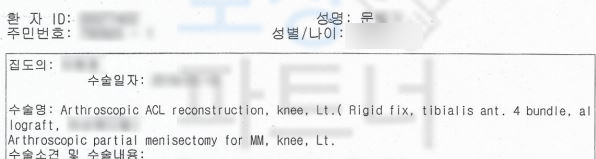

위 초진 기록지를 보시면 왼쪽 무릎의 통증을 호소하신 것과 사고 경위가 대략적으로 언급되어 있습니다. 이 사고로 받은 진단은..!

전방십자인대 파열 좌측 s8352

십자인대 재건술을 받으셔야 했죠. 십자인대 재건술을 받았음에도 거동 시에무릎이 흔들거리거나 다리가 툭툭 떨어지는 느낌이 있다면 후유증 보상 즉 후유장해보상 알아보세요.